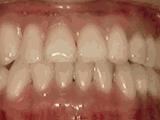

第四种

牙列拥挤,牙槽骨过窄,牙齿没有足够空间,只好前后左右高低上下乱长,经过矫正后的牙齿是这样的~